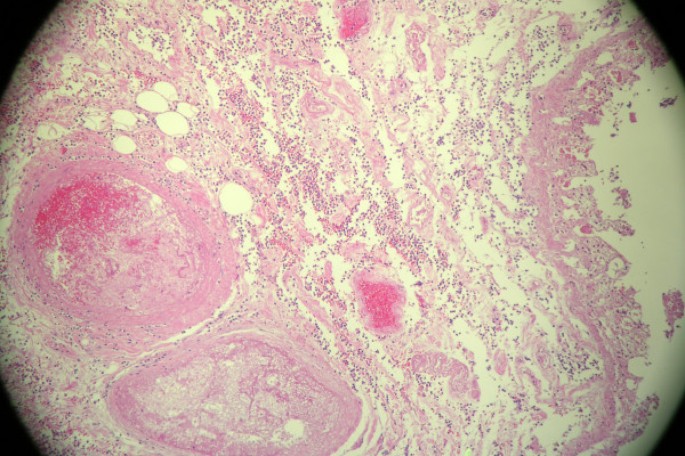

On examination, blood pressure was 170/75 mm Hg and respiratory rate 24/min and laboured. He required accessory muscles for respiration. There were bilateral rales over both lung fields. His heart and abdominal examination was not remarkable and there was no peripheral edema. Serum sodium was 143 mEq/L; potassium, 5.9 mEq/L; blood urea nitrogen, 70 mg/dL; serum creatinine, 5,0 mg/dL; albumin, 3.7 g/dL. Hemoglobin level was 11.8 g/dL, hematocrit 35%, and white blood cell (WBC) count was 12 × 103/μL. Urinalysis showed proteinuria, with protein of 30 mg/dL, and moderate blood, with 20 to 30 red blood cells/high-power field. Chest X-ray showed pulmonary edema. Renal ultrasound revealed small right kidney. Patient refused dialysis treatment and was admitted to ICU. On the third hospital day he remained volume overloaded and hypertensive despite of intravenous furosemide, his creatinine rose to 5.5 mg/dL, urea nitrogen to 91 mg/dL, and patient consented to HD. After two HD sessions, his volume status and blood pressure improved but the patient complained of mild right upper quadrant abdominal pain and nausea at the end of his second treatment. He was afebrile and denied having diarrhea, chills or vomiting. On examination, his abdomen was slightly distended with hypoactive bowel sounds and right upper quadrant tenderness. An abdominal computer tomography (CT) scan revealed distended gallbladder with sludge and diverticulosis of the sigmoid colon. Upper endoscopy (EGD) showed gastritis. Intravenous antibiotics with ceftriaxone and metronidazole started for presumed acute acalculous cholecystitis. Over next week the patient had few hypotensive episodes during HD with systolic blood pressure of 70–80 mm Hg associated with marked increase of abdominal pain. Rebound abdominal tenderness and leukocytosis with WBC count of 24.5 × 103/μL with 90% neutrophiles noted. Repeated abdominal CT scan with intravenous contrast showed mild ascites and increased small bowel distention (Figure 1). Hepatobiliary (HIDA) scan was unremarkable. A diagnostic laparoscopy converted to exploratory laparotomy revealed ischemic small bowel of the distal ileum with at least two areas of necrosis that was resected with anastomosis and insertion of feeding catheter per jejunostomy tube. Histopathology examination of the small bowel demonstrated transmural ischemic necrosis with hemorrhages and non-occluded mesenteric artery (Figure 2). Patient maid a steady recovery, and was discharged on the 11th post-operative day.